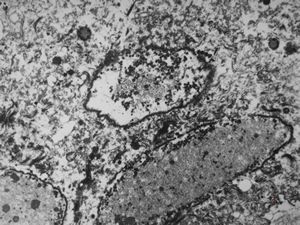

jejunal mucosa - contracted smooth muscle cells

contracted smooth muscle cells in an intestinal villus